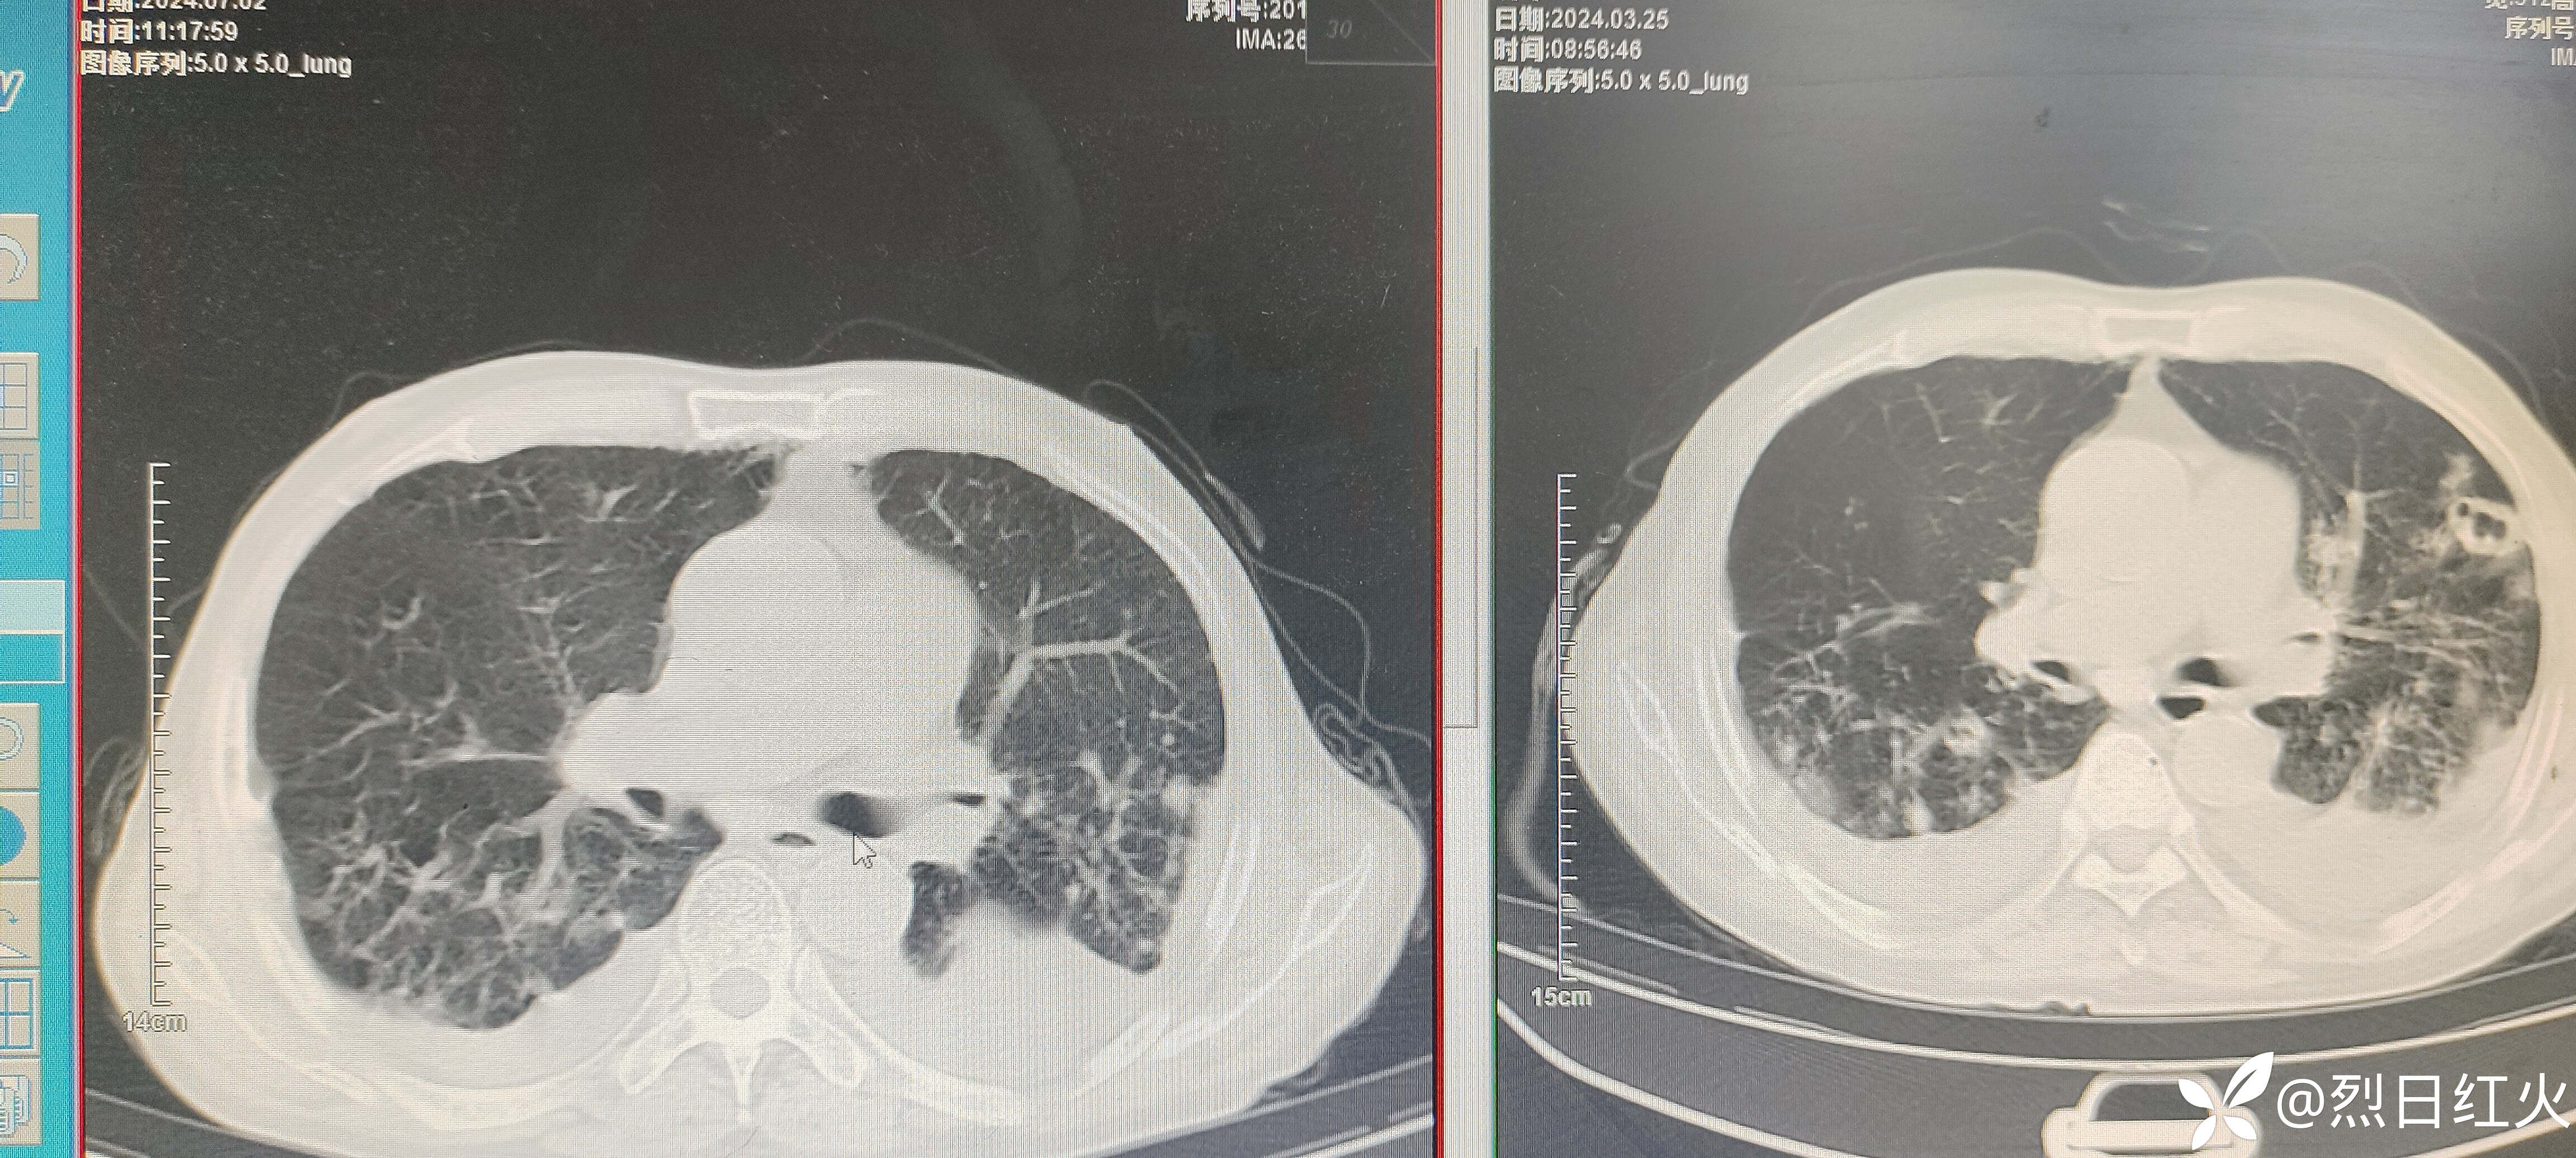

该病历患者入院后病情缓解,以后症状逐渐加重,治疗经过有不足之处望指正!2024-07-02复查胸部CT与2024-03-25胸部CT对比,病灶较前明显吸收。如下图:

复查胸部CT

CT平扫:双侧胸廓对称,双肺纹理增多、紊乱,肺野透光度增强,双肺见多发小结节样及条索状稍高密度影,边界清楚,双肺呈对称性分布,以双肺上叶中内带为著,双肺见多发斑片状稍高密度影,边界欠清,纵隔气管居中,纵隔内未见明显肿大淋巴结影,心影未见明显增大,心包未见明显增厚,双侧胸腔见弧形稍低密度影,胸壁软组织未见明显异常,扫描范围内:肝内见多发圆形低密度影,CT值约6HU,较大直径约2.8cm。

1、右肺中叶、下叶及左肺感染性病变治疗后复查,与2024年3月20日CT对比,病灶有所增加。

2、慢性支气管炎、肺气肿。

3、双肺改变,请结合其职业史,建议进一步检查,除外尘肺。

4、双侧胸腔积液。

5、肝内多发囊性占位性病变,建议上腹部CT平扫。